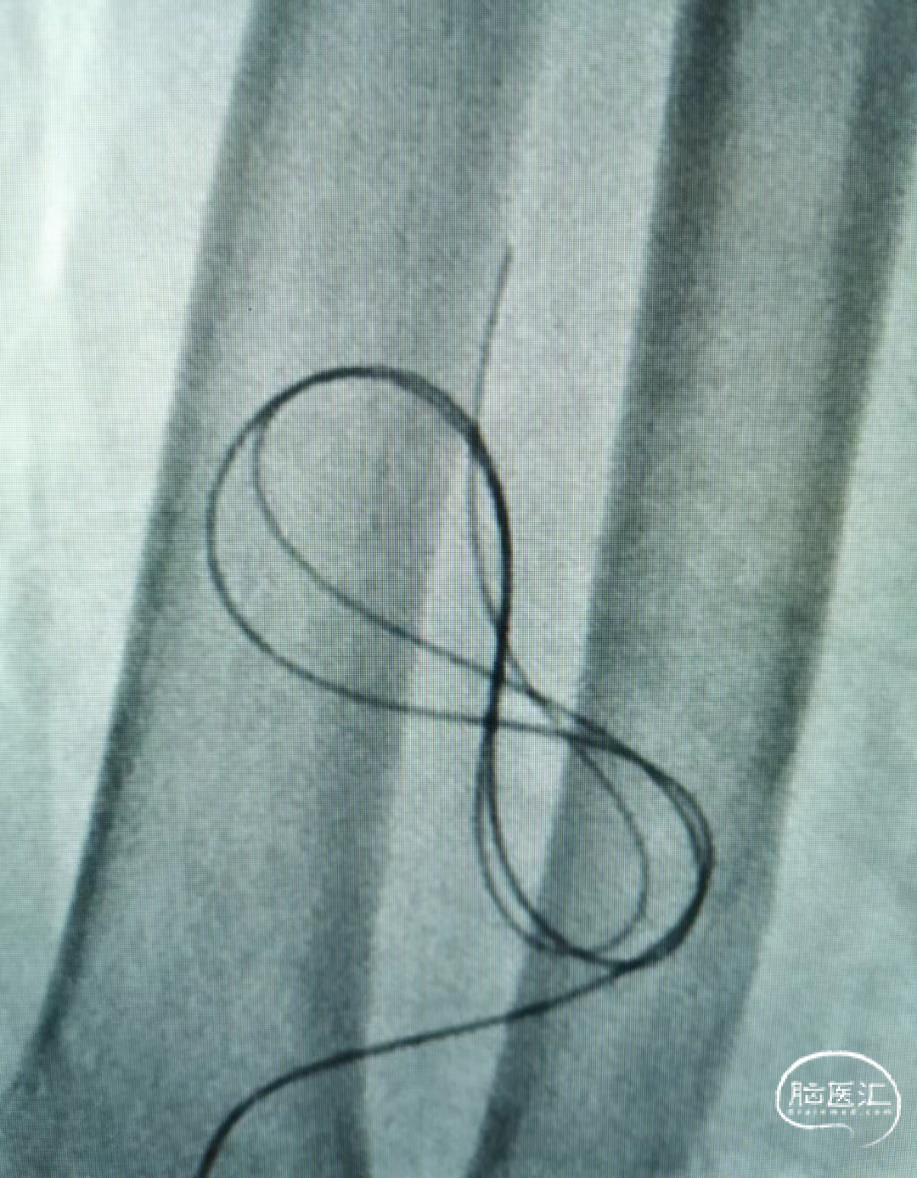

高位桡动脉微导丝植入困难,同轴技术

左侧桡动脉入路(微导丝S塑型)

1. 材料:6F桡动脉穿刺器鞘、加奇105cm的中间导管、0.029inch的Fastrack微导管、0.014inch微导丝

2.技术:中间导管+Fastrack的同轴技术+微导丝S塑型

S塑型的微导丝超选椎动脉开口

微导丝-Fastrack微导管-中间导管顺次同轴引导到位